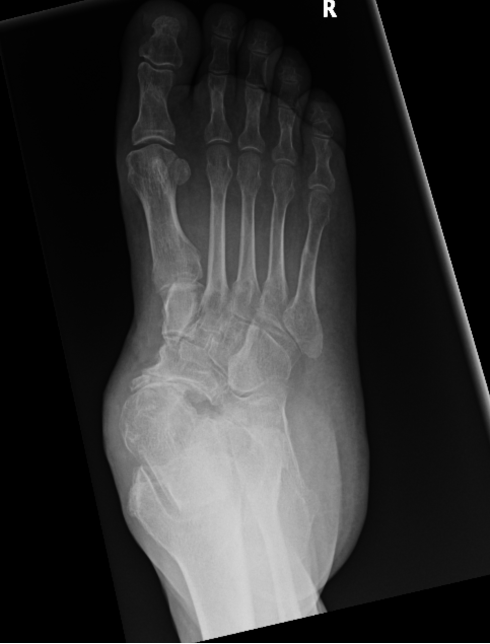

Figure 1: standing Xrays demonstrating significant hindfoot arthritis with severe flatfoot deformity